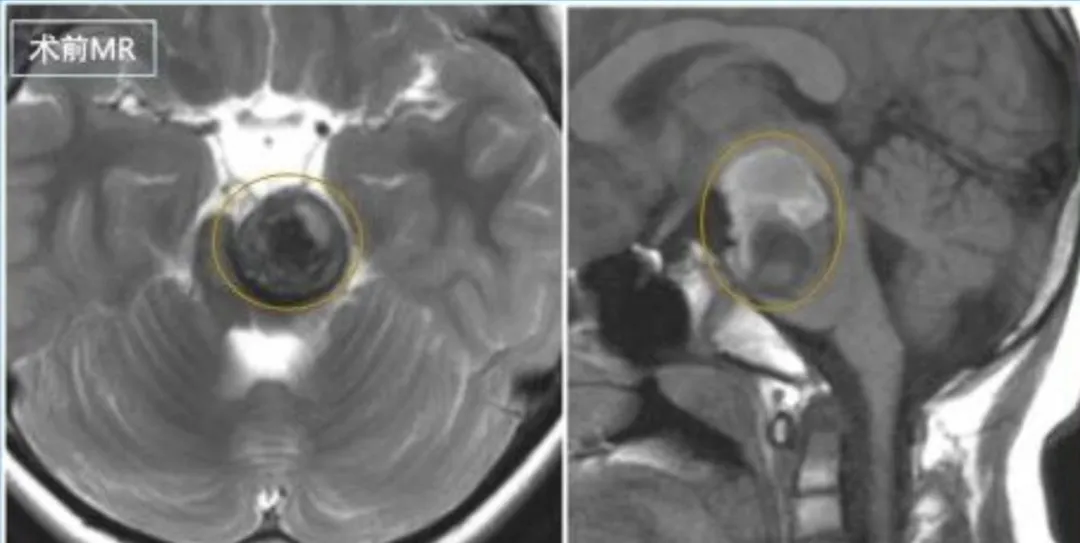

脑干手术成功率多大? 偏瘫、走路不稳、脸歪口斜,我从没想过我的脑干海绵状血管瘤会让我情况如此严重。当医生指着我的影像告诉我,我的血管畸形已经长得非常大时。看着那个感觉都要...